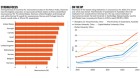

Ageing and burden of neurological disorders

Human ageing is mainly reflected in the aspects of brain ageing and degradation of brain function. The number of people aged 60 years and over worldwide was around 900 million in 2015 and is expected to grow to two billion by 2050. 3 With the increases in population ageing and growth, the burden of neurological disorders and challenges to the preservation of brain health steeply increase. People with neurological disorders will have physical disability, cognitive or mental disorders, and social dysfunction and be a large economic burden.

Globally, neurological disorders were the leading cause of disability adjusted life years (276 million) and the second leading cause of death (9 million) in 2016, according to the Global Burden of Diseases study. 4 Stroke, migraine, Alzheimer’s disease and other dementias, and meningitis are the largest contributors to neurological disability adjusted life years. 4 About one in four adults will have a stroke in their lifetime, from the age of 25 years onwards. 5 Roughly 50 million people worldwide were living with dementia in 2018, and the number will more than triple to 152 million by 2050. 6 In the following decades, governments will face increasing demand for treatment, rehabilitation, and support services for neurological disorders.